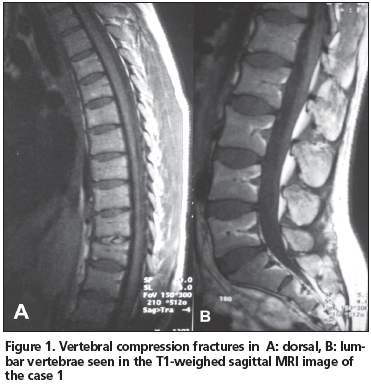

Compressive fractures were detected in nearly all lumbar and thoracic vertebras on magnetic resonance imaging (MRI), requested elsewhere before admission to our clinic; the fractures were most prominent in the lower thoracic and upper lumbar region (Figure 1). Bone mineral density (BMD) examination obtained with dual-energy X-ray absorbtiometry (DXA) (DXA-Lunar) revealed a 34% loss in the lumbar spine and 30% loss in the femoral region with respect to her age group (L2-4 Z-score -3.4, femur neck Z-score -2.4).